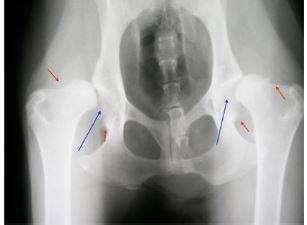

- Dysplázia bedrového kĺbu - ochorenie typické pre stredne veľké a veľké plemená psov.